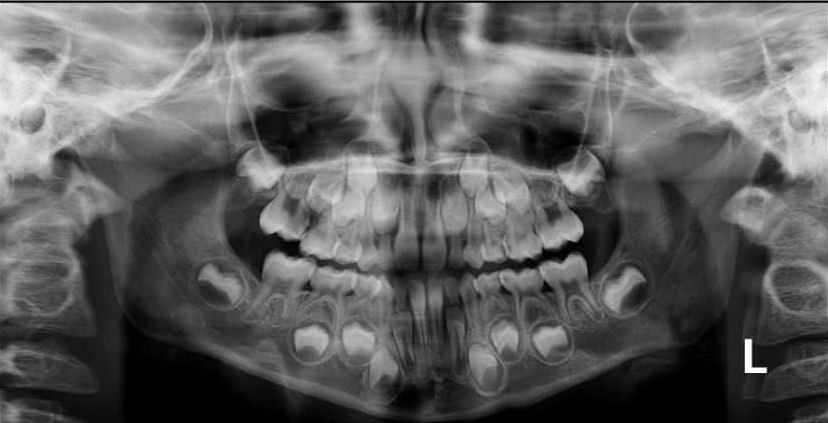

3. How old is the patient with the following X ray?